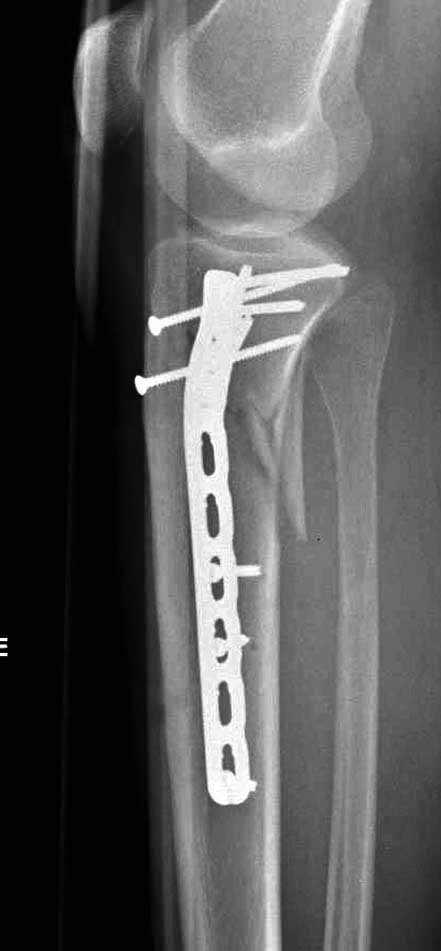

Это мероприятие превращает перелом в простой диафизарный, который легко можно фиксировать гвоздем. Шурупы надо установить сзади предполагаемого места введения гвоздя.

Для изолированных переломов медиального тибиал плато, фиксацию можно провести “медиальной пластиной”. Некоторые компании, например Smith & Nephew делают медиальные и медиально-задние пластины, но они мягкие, и легко можно создать нужный контур. Жесткость создается за счет фиксации жесткими пластинами, например экстра артикулярной пластиной для дистального плеча от Synthes. Медиальный доступ тоже не из легких, надо работать между pes and medial gastroc.

Частая ошибка, когда фиксацию двух колонного перелома проводят одиночной пластиной, т.е с одной стороны, и такая фиксация не удерживает, происходит вторичноое смещение. Необходимо нейтрализовать второй пластиной или дополнительным наружным фиксатором.

Если у вас, кроме пластины, нет другого альтернативного варианта, тогда, учитывая мягкотканые проблемы с наружной стороны, я бы рекомендовал операцию делать в два этапа. Преимущества, сперва репозиция и фиксация перелома с медиальной стороны, а затем, после улучшения состояния мягких тканей, зафиксировать с латеральной стороны. Современные пластины имеют латеральный Jig для перкутанных мини доступов.

В приложении этапы фиксации Both Column Fx и пластиной Synthes для плеча при переломе медиального мыщелка.